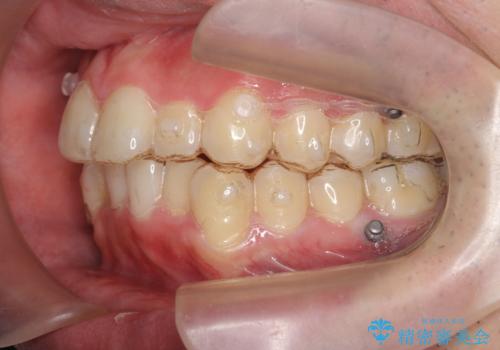

- 矯正装置

- インビザライン

奥歯を後ろに下げるのに、上下左右に矯正用ミニスクリューを入れています。